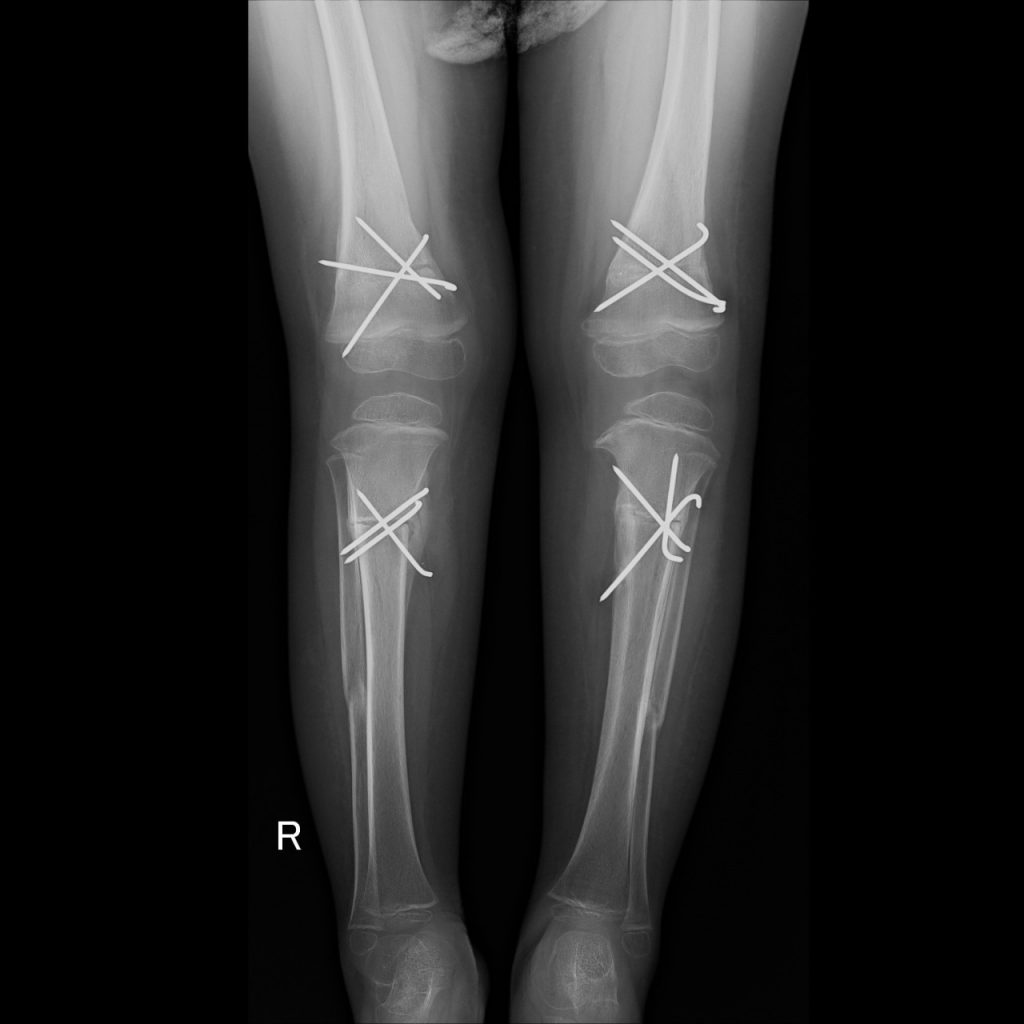

BURNT OUT RICKETS

Rickets is a disease of childhood characterized by deformities of the skeleton. It is usually the result of a vitamin D deficiency. Less commonly, it is seen as a result of a phosphate metabolic abnormality. One would not expect vitamin D deficiency in a sunny country like South Africa, but with the change of lifestyle it does become more prevalent.

These are the pre- and post-op XRs of a two-year-old with burnt out vitamin D deficient rickets.